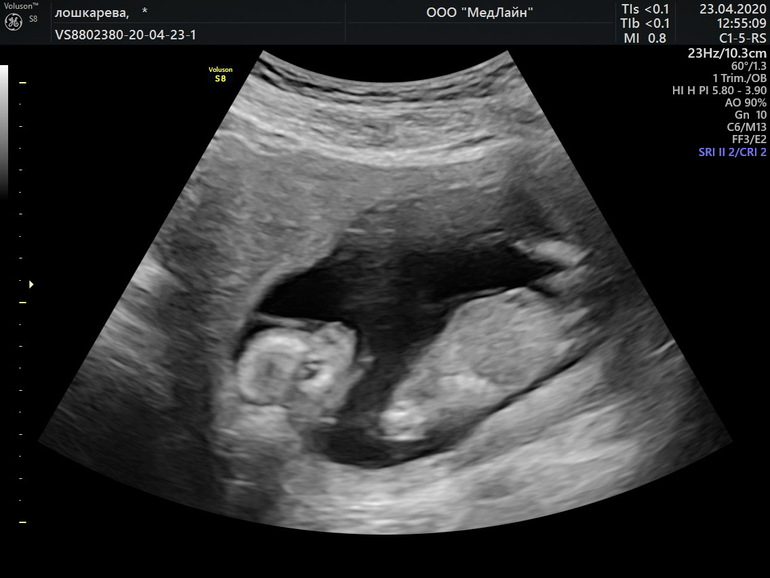

УЗИ, КТГ, доплерДевочки, можно ли по этим фото узнать пол ребёнка? Врач не стал говорить, так как боялся ошибиться

Вот, девочки, не пойму- на первом фото ножки раздвинуты или Нет. Муж конечно хочет сына) а мне всё равно)))